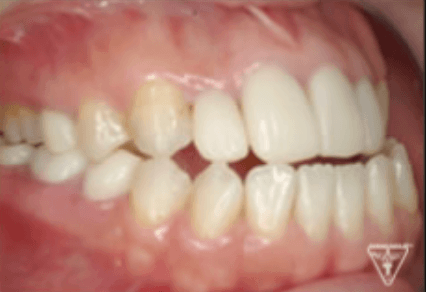

40代女性:反対咬合の治療(ゴムメタル矯正)Skeletal Class Ⅲ Mesio-fecial Type Case

治療前